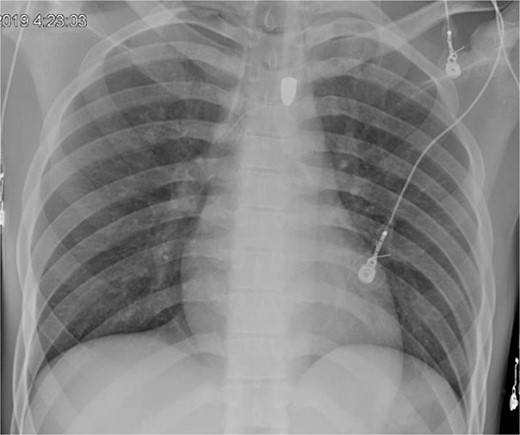

A 21-year-old male with a GSW to the left scapula presented to our Level 1 trauma center. He was stable but had flaccid paralysis and no rectal tone. A chest X-ray showed a bullet in the upper mediastinum (Fig. 1), prompting a computed tomography (CT) angiogram. The CT revealed a C6 cervical spine fracture, epidural hematoma, pneumomediastinum, and the bullet in the mediastinum at approximately the level of T3, but no hemorrhage (Fig. 2). Immediate upper endoscopy and bronchoscopy under general anesthesia were normal. He was extubated and monitored in the trauma ICU.